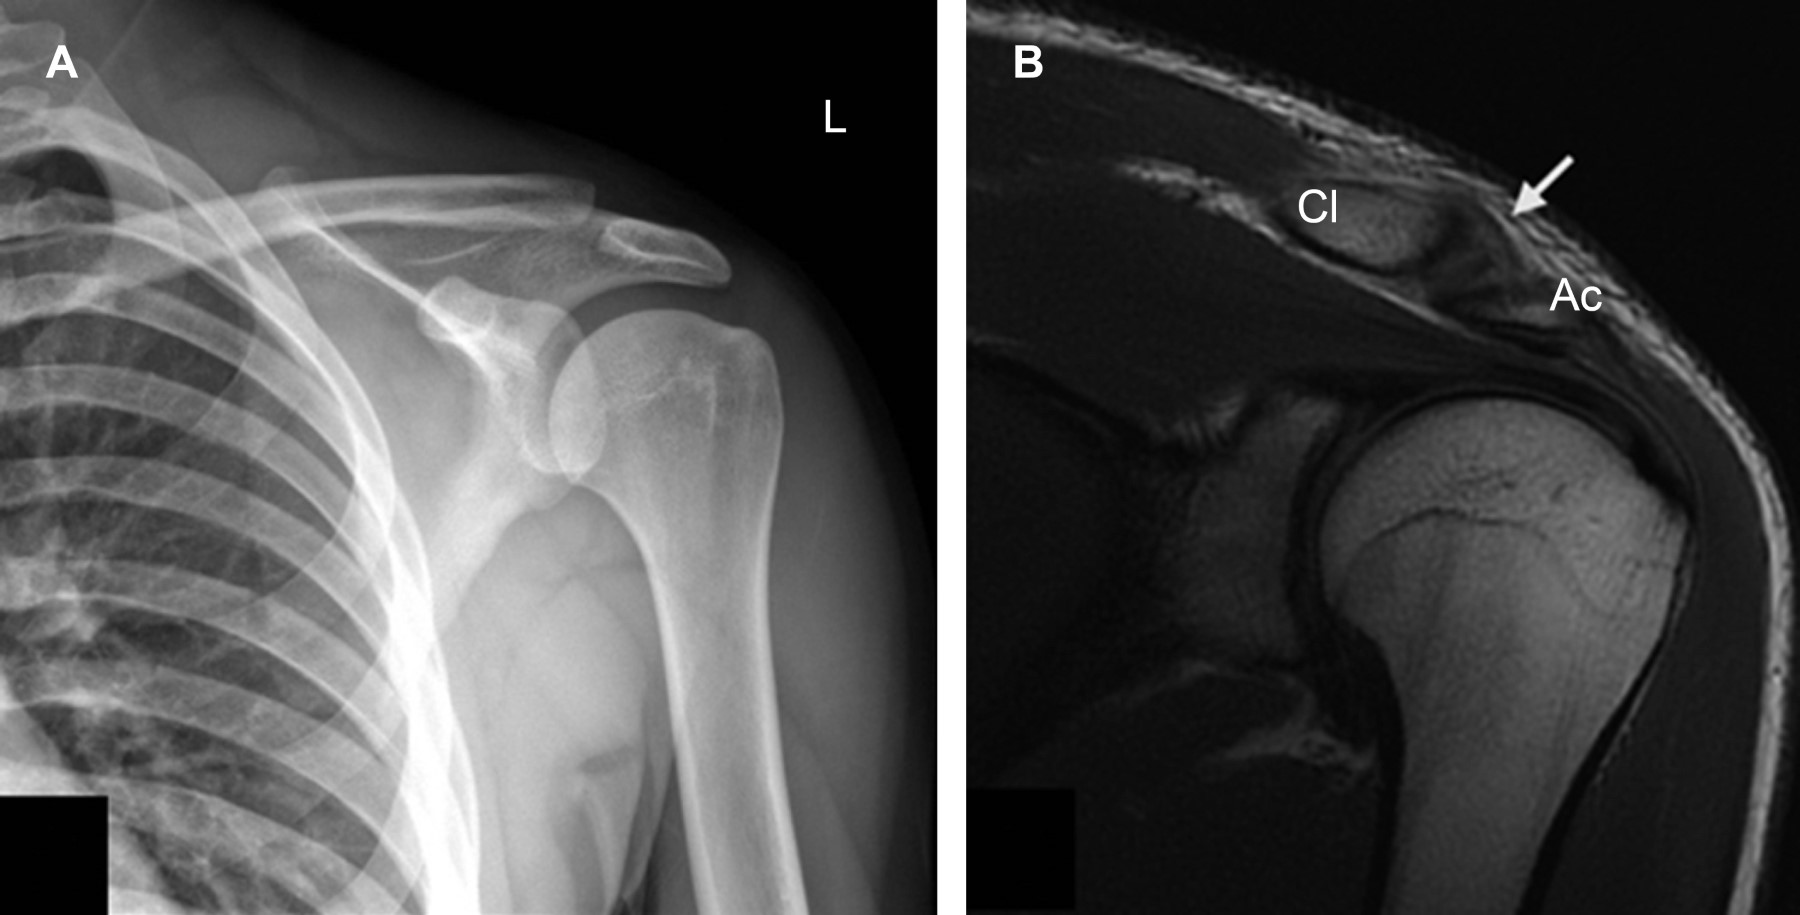

Osteolysis of the distal clavicle: underdiagnosed cause of shoulder pain

Introduction: osteolysis of the distal clavicle is an underdiagnosed cause of shoulder pain. There is no reported incidence in the literature. It is most frequently caused by repetitive microtrauma in patients who perform weightlifting or overhead sports. Case report: 22-year-old male with shoulder pain of one week of evolution. Conclusion: due to the increase in sports practice, osteolysis of the distal clavicle will be an increasingly seen entity, so it is essential to recognize the clinical picture and magnetic resonance findings, being the edema of the bone marrow the most frequent and characteristic.

Figure 1